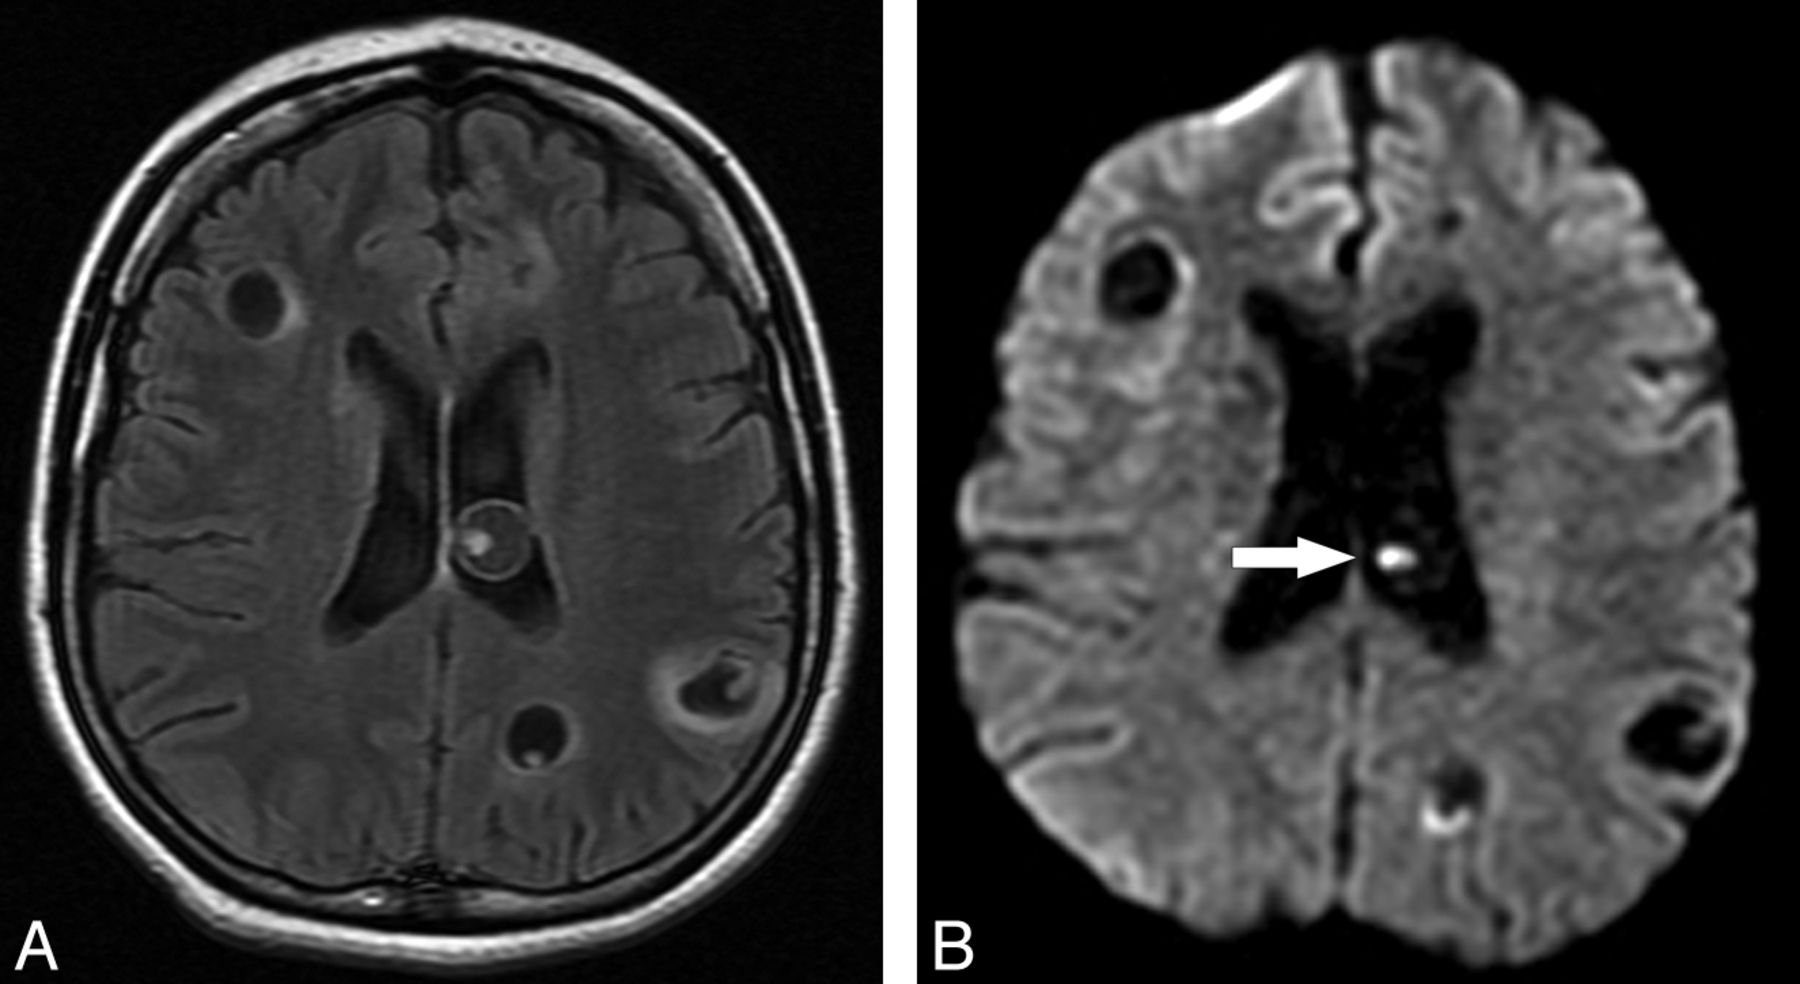

All cystic lesions judged to be in the vesicular stage showed high signal on T2WI and low signal on T1WI and FLAIR, paralleling CSF signal on all sequences. There was no evidence of relevant contrast enhancement or perilesional edema. DWI demonstrated low signal in all lesions, like CSF. However, in 41 of 139 lesions in the vesicular stage (29.49%), there was visible evidence of the small eccentric dot or comma-shaped DWI hyperintensity suggestive of the scolex, which presented iso-/hypointensity in ADC maps compared with brain parenchyma (Fig 1).

Axial FLAIR (A) and axial DWI (B) images show 3 lesions in both frontoparietal areas (arrow and arrowheads in A); there is 1 right parietal lesion (arrow on A), compatible with NCC in the vesicular state. In this lesion, the scolex is clearly seen on DWI as a hyperintense eccentric dot, but it can also be appreciated in the other 2 images. ADC map (C) discloses the scolices as iso-/hypointense dots.